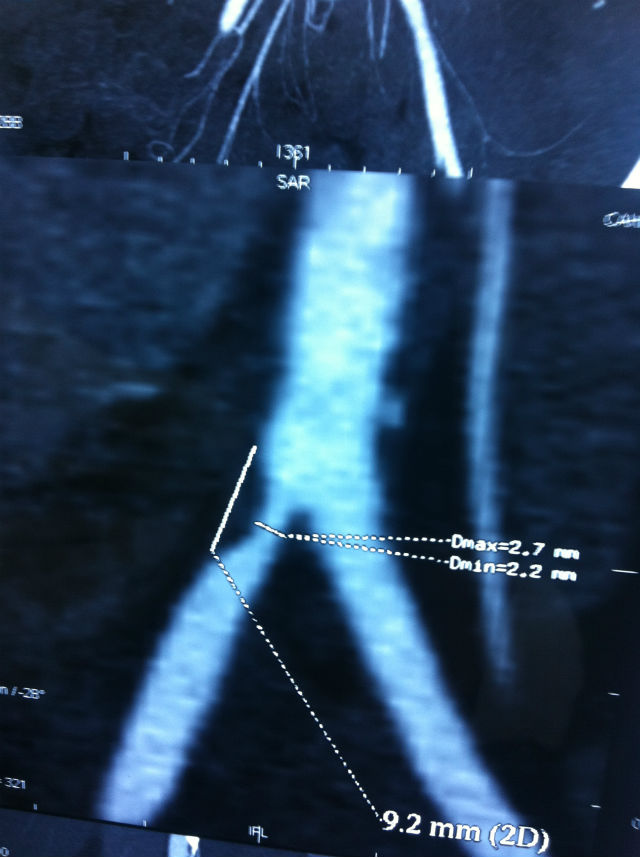

periferik_anjiyo Published 3 Ekim 2015 | By Cafer Abbasoğlu Full size is 640 × 857 pixels Op.Dr.Cafer Abbasoğlu » « lazer_4